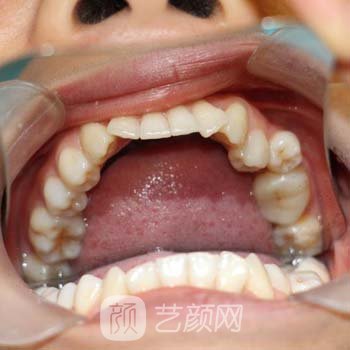

医生检查了整个口腔后,我扫描了牙齿,我可以在电脑上完全看到我在牙齿的安排。医生说我的情况并不是特别糟糕,所以在牙齿,矫正的时间不必那么长。天津市口腔医院整形科做牙冠多少钱?果好吗?价格表费用标准在线一览